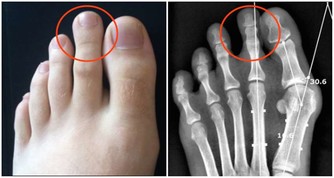

其中骨關節炎和類風濕關節炎這兩種是比較常見的,來看看二者的區別

骨關節炎:軟骨磨損

類風濕關節炎:滑膜病變

骨關節炎:僵硬、疼痛、不能握拳、大拇指不靈活、有硬結

類風濕關節炎:晨起後嚴重,活動後好轉

骨關節炎:X線檢查

類風濕關節炎:風濕4項、X線檢查